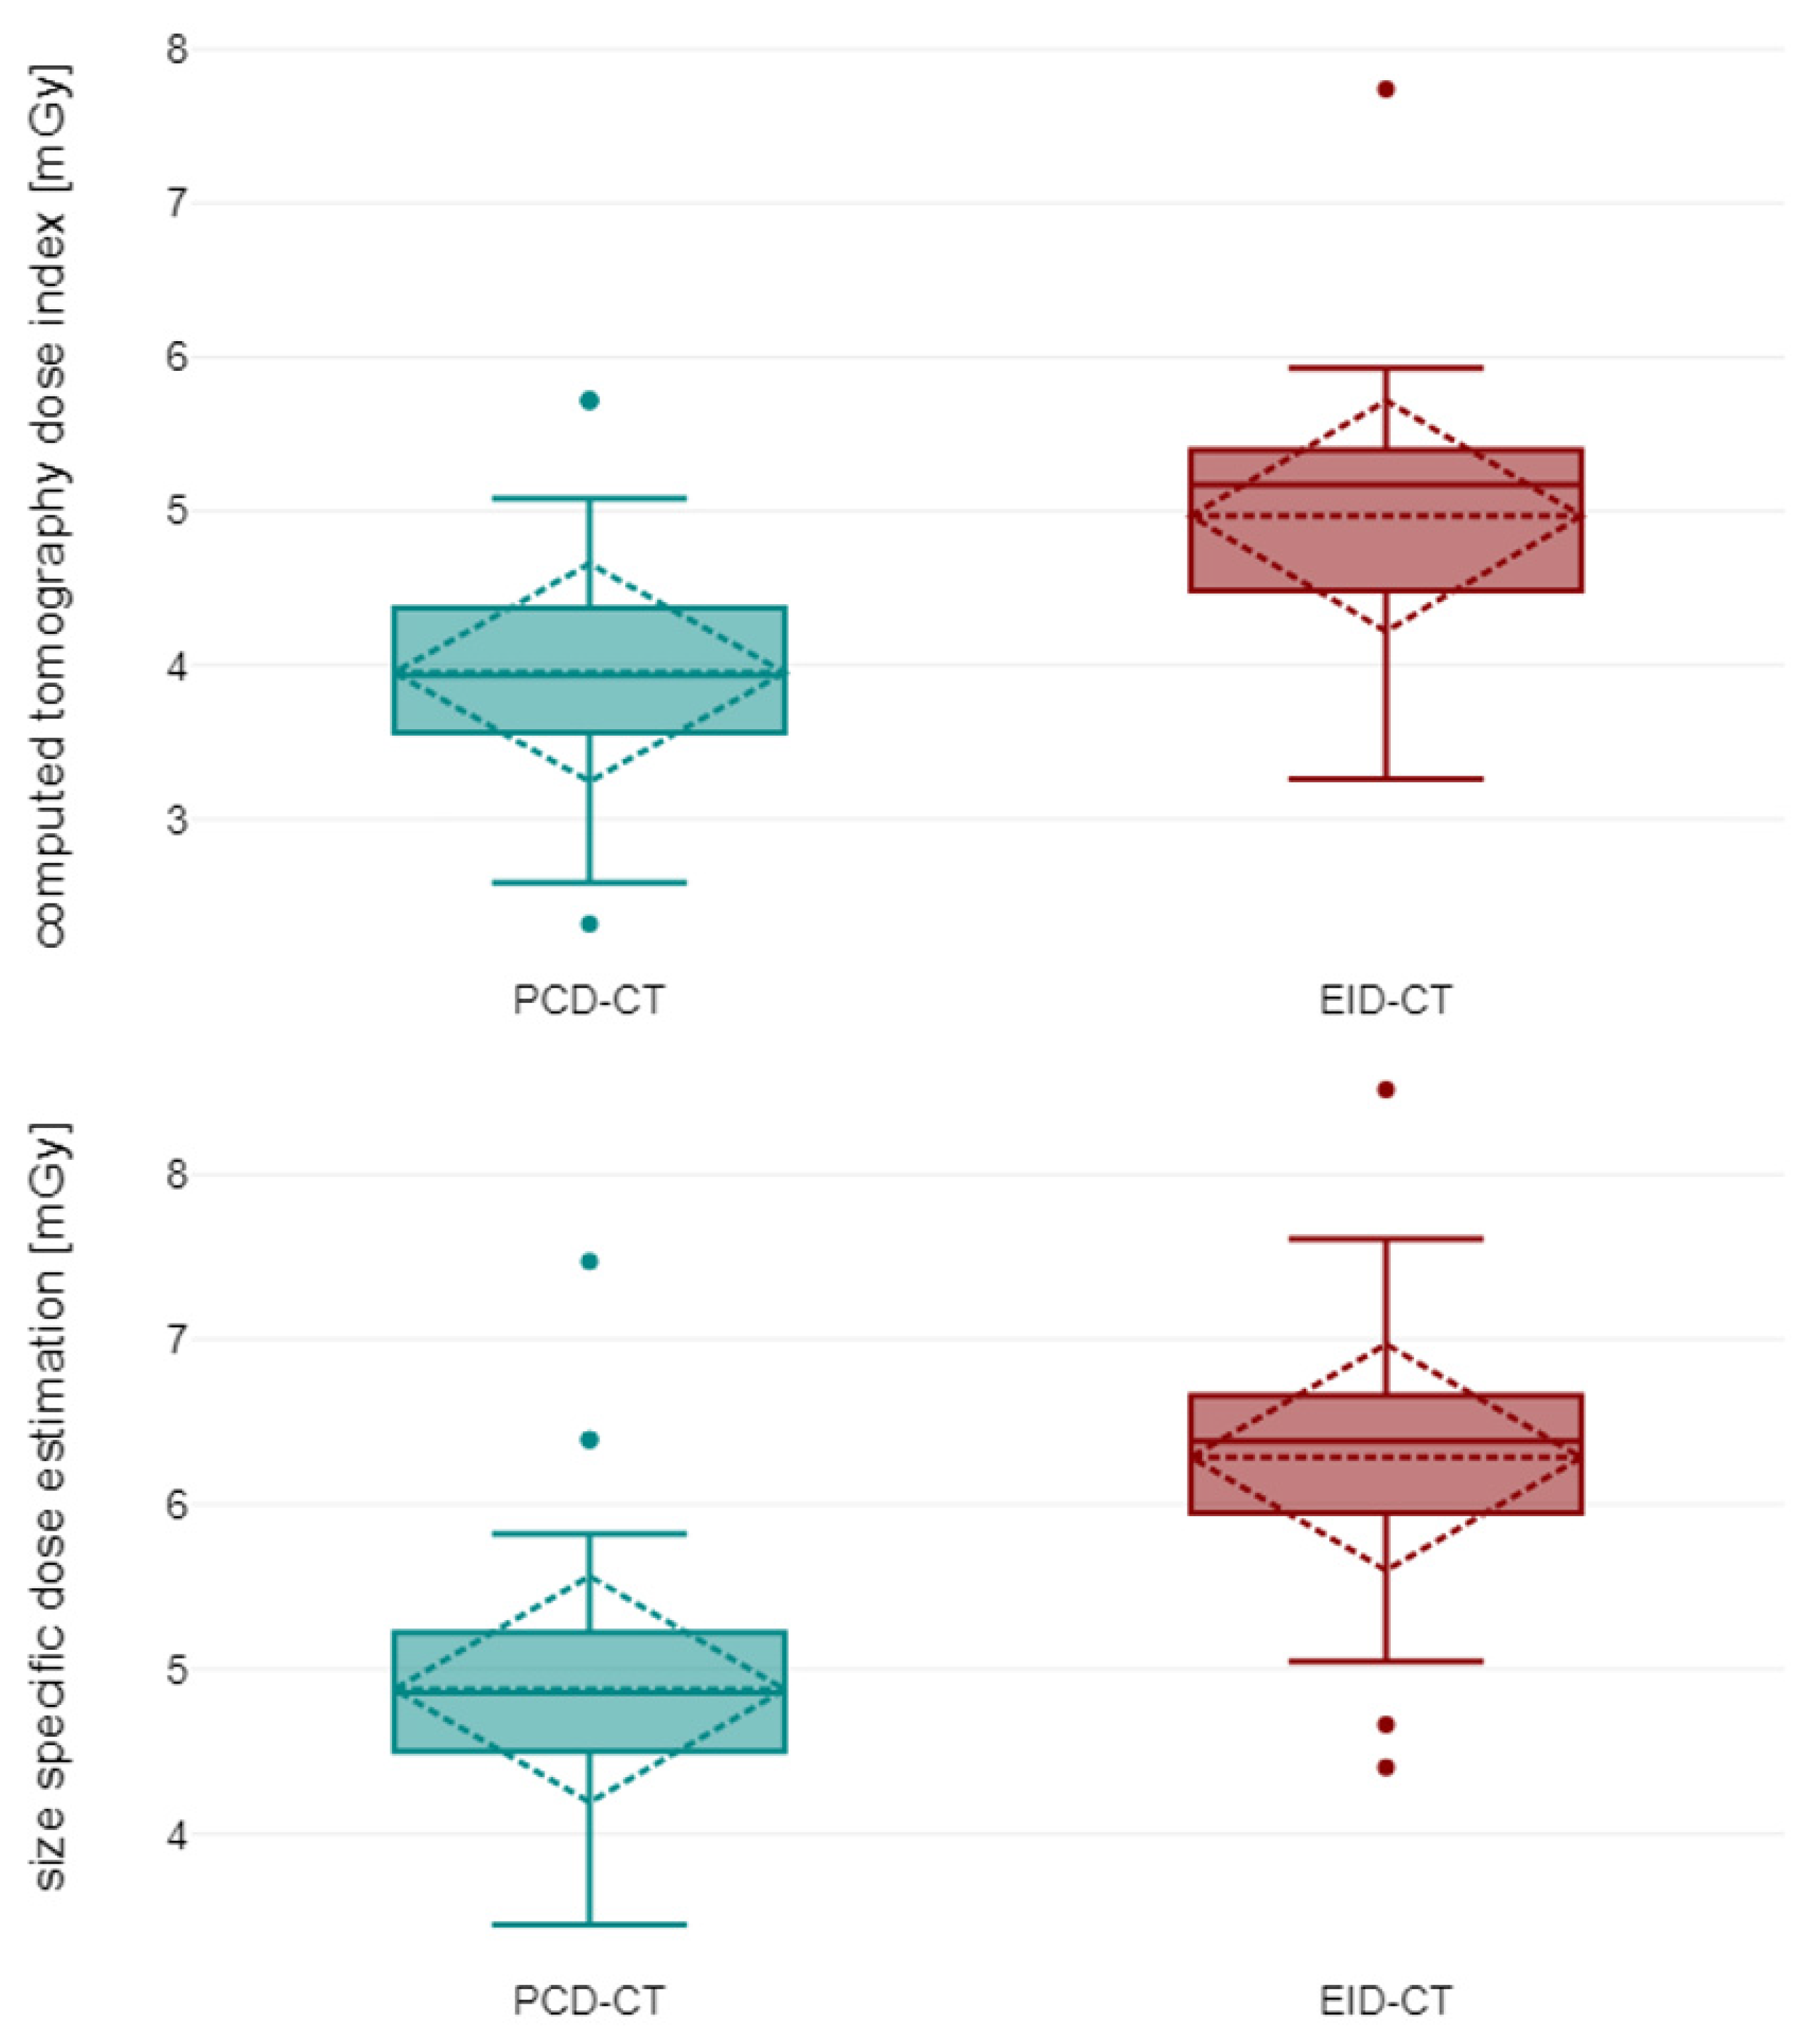

3.1. Patient Characteristics and Radiation Dose

3.2. Objective Image Quality